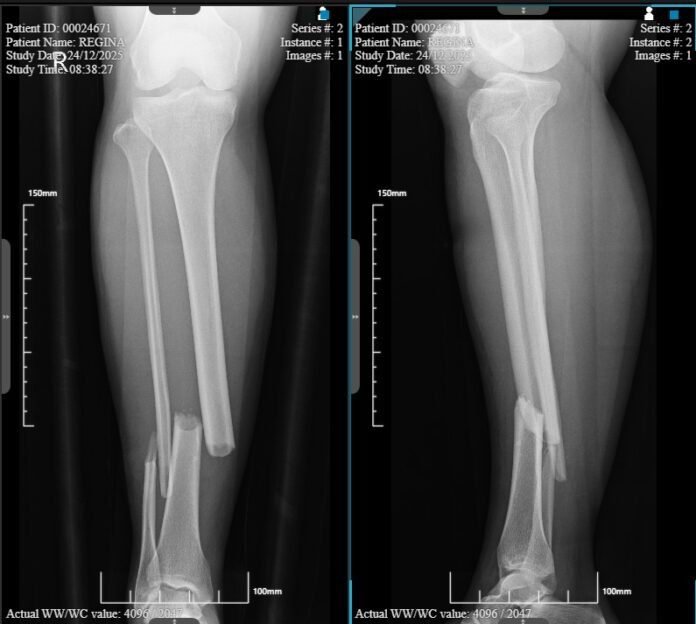

Korban diketahui bernama Ellyas dan istrinya Regina warga Kecamatan Delta Pawan Ketapang Sukaharja Jalan PLTD Gg. Almahkrub RT.25/RW.26..Saat kejadian, keduanya tengah dalam perjalanan pulang dari arah Sandai menuju mess PT LTW yg berada di wilayah administrasi Desa Pendamar indah Randau

Menurut keterangan keluarga korban, mobil PLN yang melaju dari arah Randau menuju Sandai menabrak sepeda motor korban hingga menyebabkan Regina terpental, sementara Ellyas mengalami pingsan dan terseret bersama sepeda motornya sejauh kurang lebih 20 meter. Benturan keras tersebut mengakibatkan korban mengalami luka serius.

Usai kejadian, korban dilarikan ke Rumah Sakit Sandai, sebelum akhirnya dirujuk ke Rumah Sakit Medika Jaya dan Rumah Sakit Umum di Pontianak untuk mendapatkan penanganan medis lanjutan.